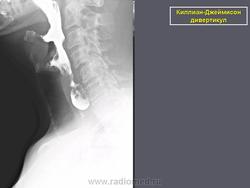

Киллиан – Джеймисон - дивертикул

Киллиан – Джеймисон - дивертикул.

Приложения:

0.radiographics_logo.png0.rg_.337125153.fig15advustoronnyaya_killian-dzhemison_divertikulov_v_76-letney_zhenshchiny.gif0.rg_.337125153.fig15bdvustoronnyaya_killian-dzhemison_divertikulov_v_76-letney_zhenshchiny.gif